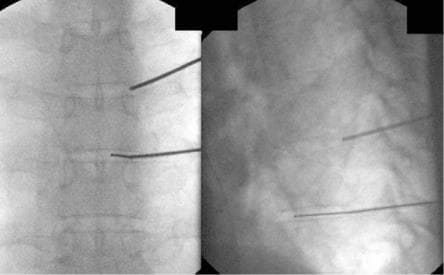

Нами розроблена методика, що дозволяє успішно проходити голкою в потрібний міжхребцевий диск і проводити в центр його лазерний промінь. Дія лазерного променя така ж, як і при лікуванні шийних або поперекових дисків.

- У найбільш складних випадках ми можемо проводити операцію не тільки під контролем рентгенапарата, а й під контролем комп'ютерного томографа